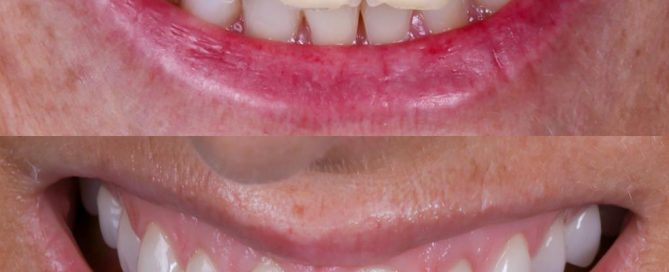

SITUACIÓN INICIAL Paciente joven con dos carillas antiguas de composite, [...]